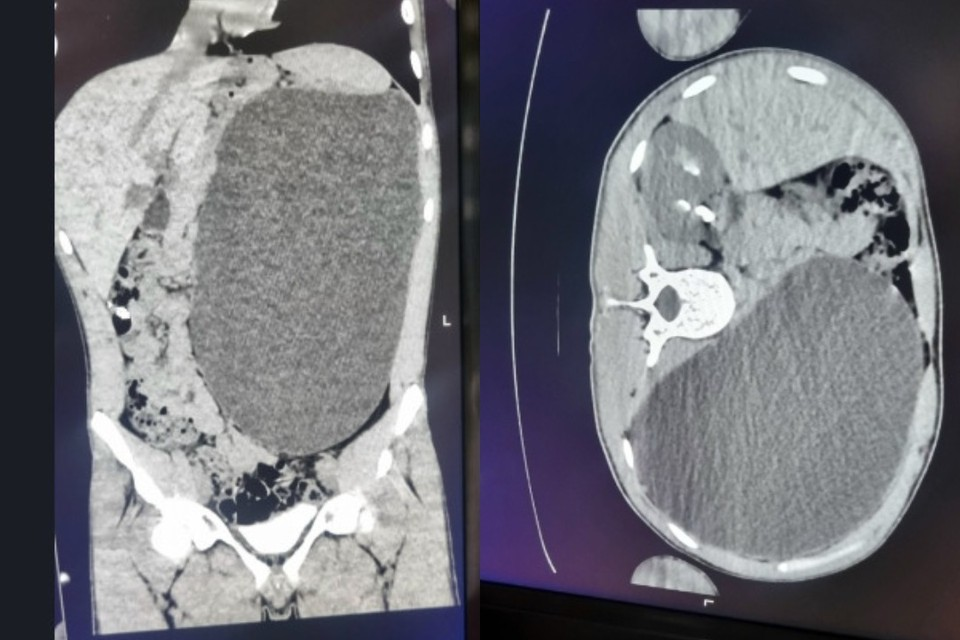

В Новосибирске во время профосмотра у 17-летнего парня выявили увеличение почки до размера пятилитровой банки. Фото: Минздрав Новосибирской области

- У нашего пациента почка достигла размеров пятилитровой бутылки! Она занимала почти весь объем живота и давила на все соседние органы, - сообщили в ДГКБ № 1.

Больная почка могла разорваться при любой травме или случайном ударе в живот, но, к счастью, все обошлось. Хирурги удалили орган и откачали скопившуюся жидкость. Сейчас пациент уже идет на поправку, а после выписки сможет приступить к работе.